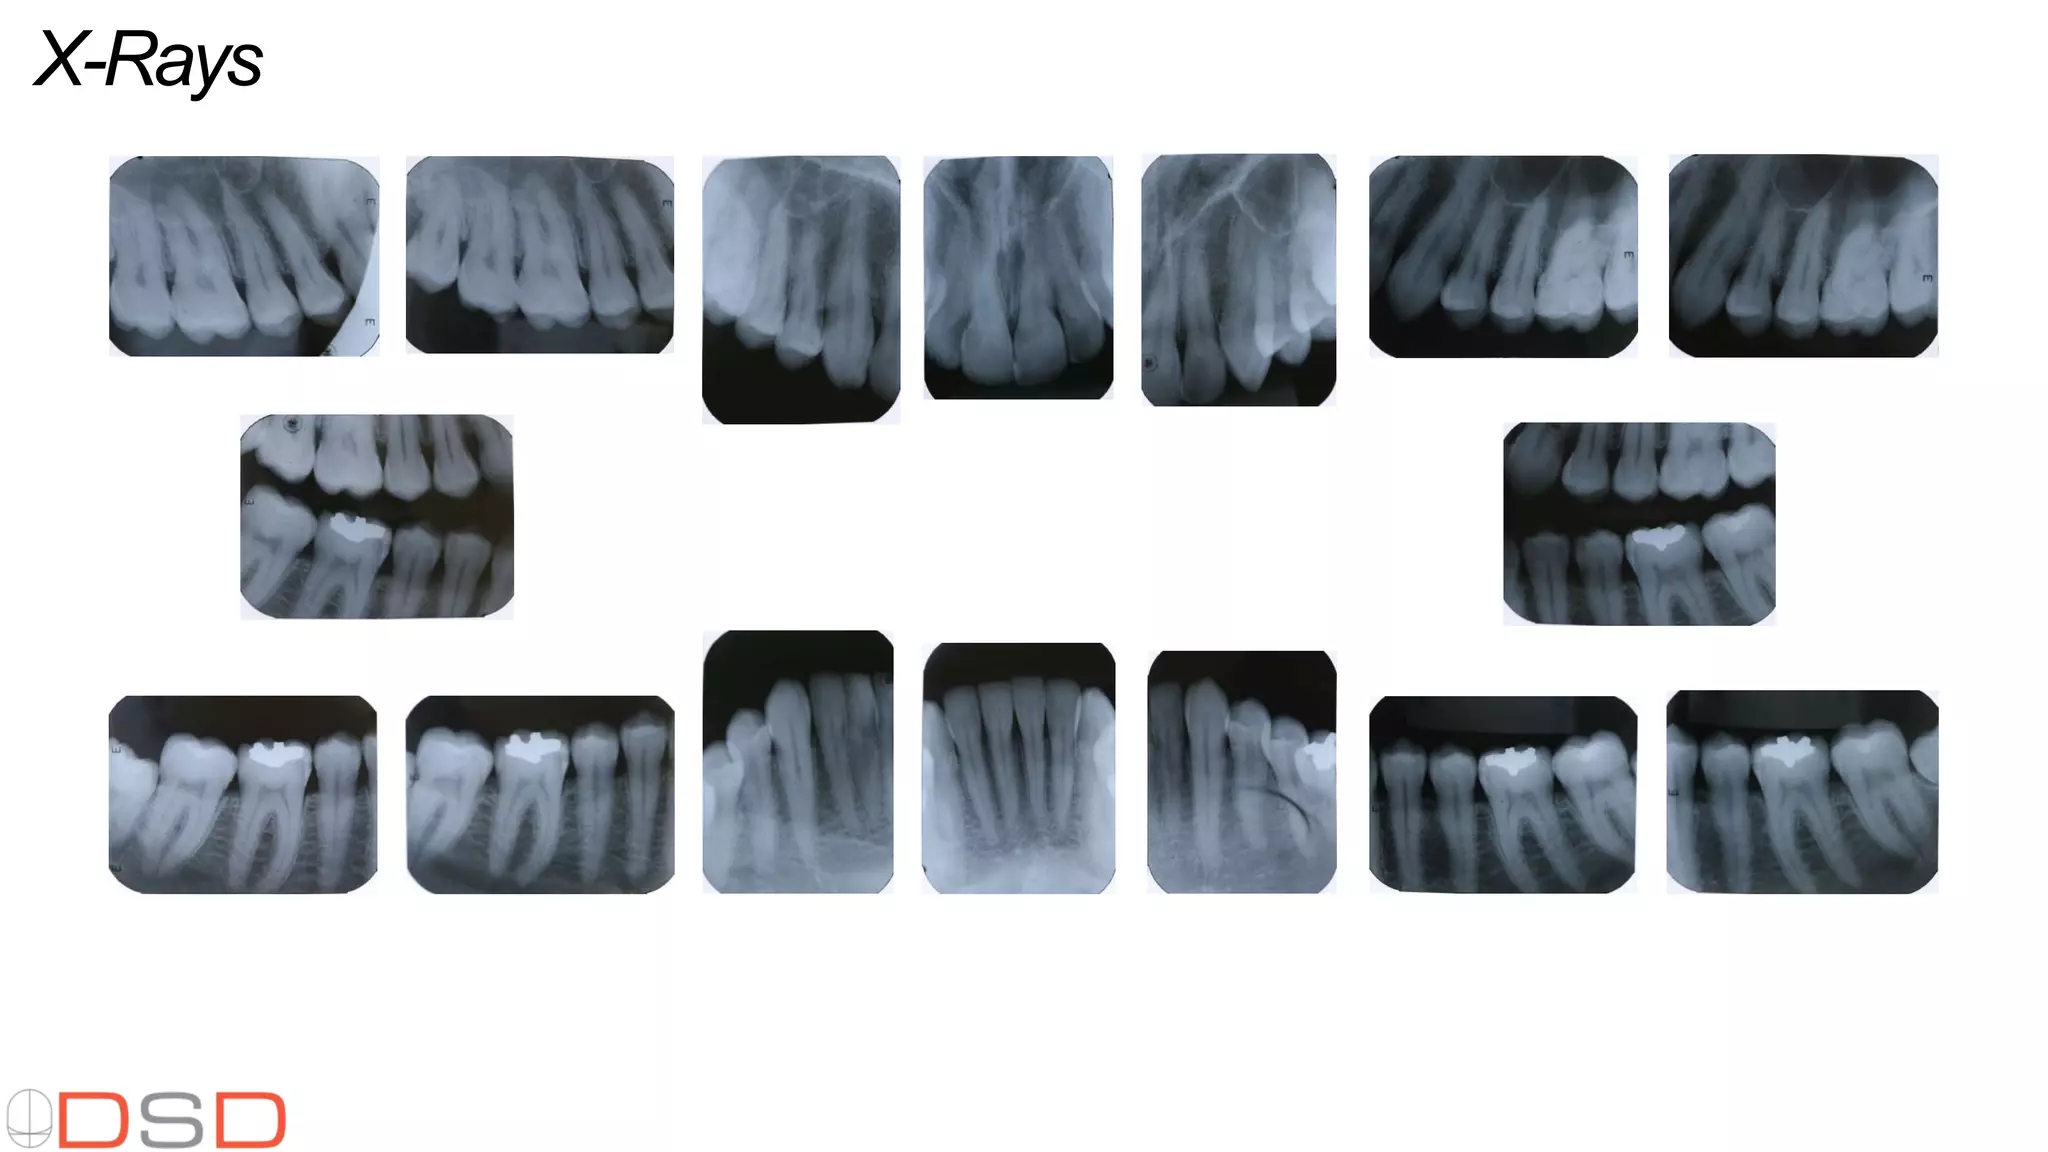

Additional visual aids including various photos, facial videos, close-up videos, functional videos, X-rays, perio charts, and panoramic images.